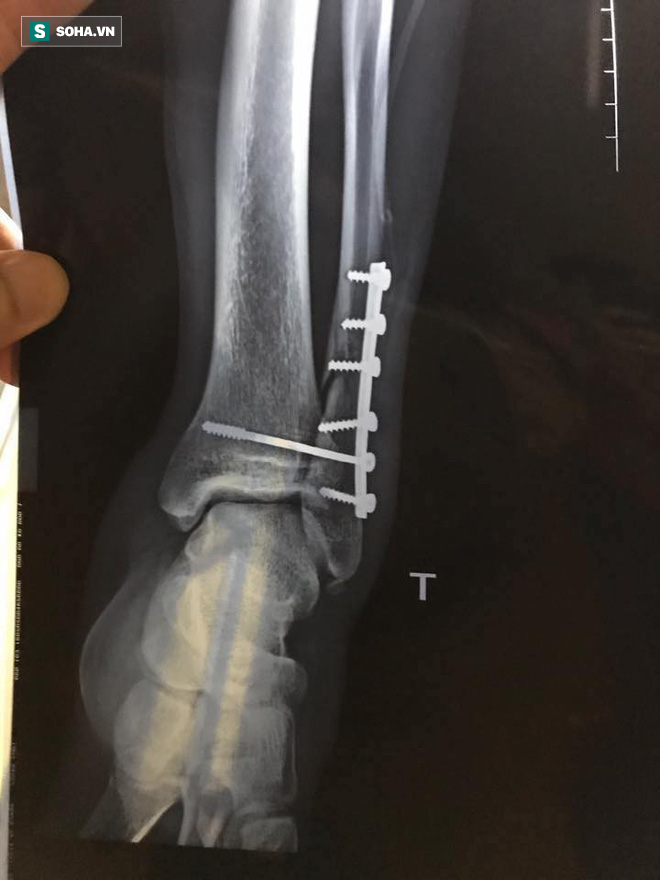

Cập nhật: Theo thông tin mới nhất, Dương Văn Hào bị gãy xương chầy, hiện đang phẫu thuật tại bệnh viện 108. Nhận định về pha vào bóng thô bạo của Tấn Tài nhưng chỉ phải nhận thẻ vàng, HLV Hoàng Anh Tuấn cảm thán:

Ảnh chụp X quang phần xương bị gãy, phải tiến hành phẫu thuật của Dương Văn Hào.